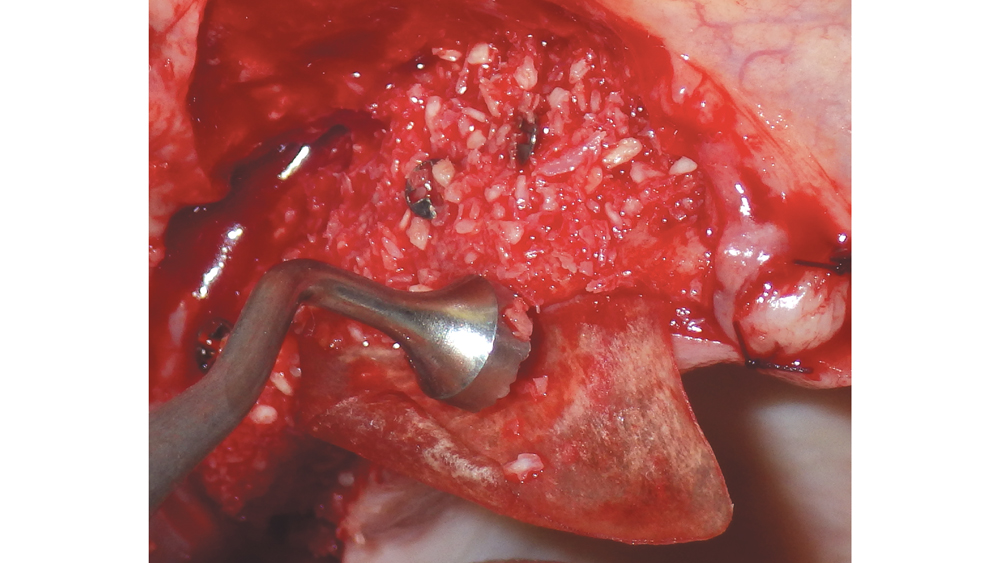

Newport Biologics™ Mineralized Cortico/Cancellous Allograft Blend (Glidewell Direct; Irvine, Calif.) possesses the optimal features of cortical and cancellous bone, with particle sizes that allow for rapid site revascularization and increased structural integrity. The cancellous bone allows for better cell migration and faster remodeling, and the cortical bone provides the space maintenance that allows the time for bone regeneration to occur. The particle size is approximately 250–1,000 microns, with a turnover rate of 4–6 months for predictable bone regeneration. Shown are various clinical GBR and lateral ridge augmentation procedures with the use of mineralized cortico/cancellous bone.

Bone graft putty is shown inserted into an osteotomy via osteotome sinus graft technique

Newport Biologics Bone Graft Putty Mineral-Collagen Composite is a calcium phosphate-based grafting material that becomes moldable upon hydration. It features a carbonate apatite structure similar to natural bone, combined with a type I collagen derived from bovine Achilles tendon. The mineral particles are dispersed within collagen fibers, forming a 3D matrix that is fully resorbed during the natural process of bone formation and remodeling. This bone graft putty is ideal for sites that require no movement of the graft material, such as areas of high muscle pulls or sinus augmentation procedures. Shown is bone putty inserted into an osteotomy via the osteotome sinus graft technique.